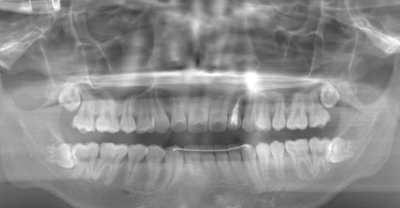

CASE 1

| 年齢・性別 | 30代・女性 |

| 主訴 | 左右に分けて親知らずを抜きたい、できれば痛くなく抜きたい |

| 親知らずのはえ方 | 完全に出ていてまっすぐはえている |

| 抜歯期間 | 15分 |

| 抜歯費用 | 約2,000円(保険内) |

| 抜歯内容 |

何度か虫歯になり痛みはないが早めに抜きたい。 完全に頭が出ているため歯ぐきを切ったり骨を削らずに抜歯しました。 根の形も単純なため抜歯自体は5分もかからず上下ともに終わりました。 術後痛みや腫れも出ていません。 抜歯後は感染をしやすいため必ず抗生物質を飲み切ってください。 |